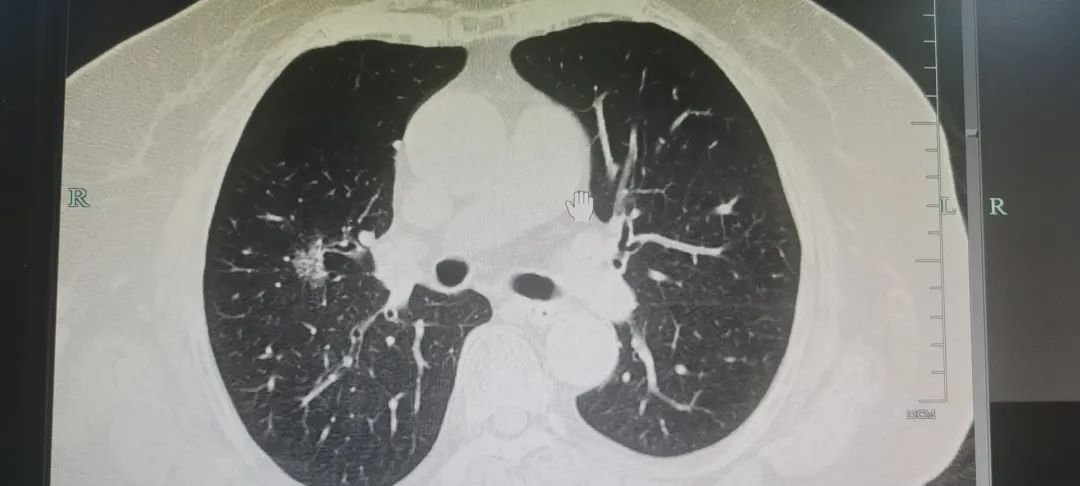

結(jié)節(jié)是一個(gè)影像學(xué)術(shù)語(yǔ),通俗一點(diǎn)就是一個(gè)小“疙瘩”,大小一般由幾毫米到 3 厘米。更大的會(huì)被叫團(tuán)塊或者腫塊。根據(jù)結(jié)節(jié)的密度大到小,可以分為鈣化、實(shí)性、部分實(shí)性及磨玻璃樣結(jié)節(jié)。

肺部小結(jié)節(jié)是指在肺部發(fā)現(xiàn)的直徑在1厘米左右的結(jié)節(jié)病變。一般將直徑小于1cm者稱為肺小結(jié)節(jié),直徑小于0.5cm叫做微小結(jié)節(jié)。